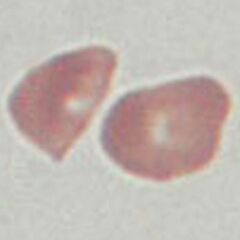

Appearance

Dense cells that have a distorted and often irregular outline; central pallor is generally absent and haemoglobin staining may be irregular within the cell. Most often there is a spectrum of forms present.

Characterised by an irregular outline and diminished or absent central pallor. As this is a damaged cell type the appearances can be very variable. But generally the haemoglobin staining-density will be irregular, and that the condensed and dehydrated cells will have reduced size. The cellular is also important since these cells generally arise in the context of other abnormal cell types – often indicating the underlying pathology.